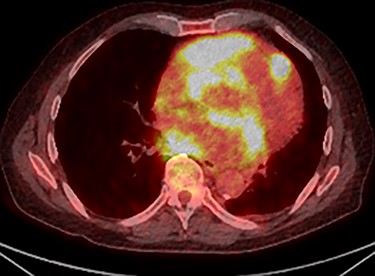

Further staging imaging was recommended by the radiology team. A CT head scan demonstrated no abnormalities, whereas CT chest–abdomen–pelvis (CAP) found significantly enlarged necrotic mediastinal lymph nodes with invasion into the pericardium and heart; bilateral adrenal nodules (suspicious for metastases) and appearances consistent with a lymphoproliferative disorder. The testicular biopsy found large lymphocytes with abundant cytoplasm and prominent nucleoli consistent with a diffuse large B-cell lymphoma (DLBCL). A positron emission tomography (PET) scan was organized at the request of the oncology team (Figs 4 and 5).

PET scan (transverse plane) demonstrating an enhancing lesion encroaching the heart with necrotic lymph nodes.